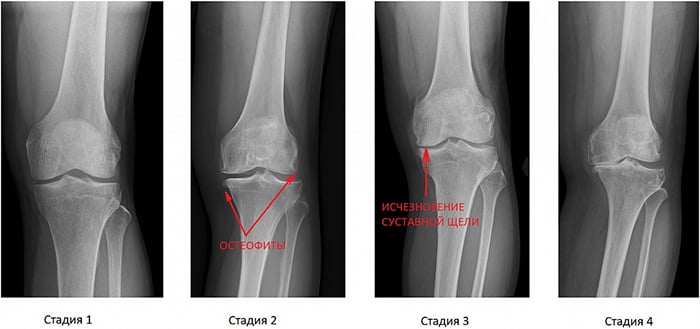

Встретила меня очень пожилая специалист. Не особо со мной разговаривая, отправила на рентген и анализы. На втором приёме за пару минут выдала диагноз — артроз, первичный или вторичный, уже не вспомню, да и какая разница.

Я как специалист-ревматолог каждый день вижу пациентов, которые долго терпели и занимались самолечением. Итог всегда один: болезнь прогрессирует, суставы разрушаются, и вернуть их в норму становится намного сложнее.